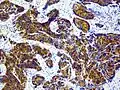

97 % aller Prostatatumoren sind Adenokarzinome, das heißt, sie entstehen aus entarteten Drüsenzellen. Ein Übergangsstadium zum manifesten Krebs wird als prostatische intraepitheliale Neoplasie (PIN) bezeichnet und entspricht einem Carcinoma in situ. Beim eigentlichen Karzinom kommen verschiedene histopathologische Wachstumsmuster vor, auch gleichzeitig nebeneinander: glandulär beziehungsweise azinär (drüsenartig), kribriform (siebartig) und solide. Das Ausmaß der Entdifferenzierung ist Grundlage des Gradings. 40–50 % der Tumoren liegen bei Diagnosestellung multifokal vor.[54]

Entdifferenziertes Karzinom

-

Knochen- und Weichteilmetastase eines Prostatakarzinoms mit immunhistochemischem Nachweis einer PSA-Expression (braun)

Knochen- und Weichteilmetastase eines Prostatakarzinoms mit immunhistochemischem Nachweis einer PSA-Expression (braun)